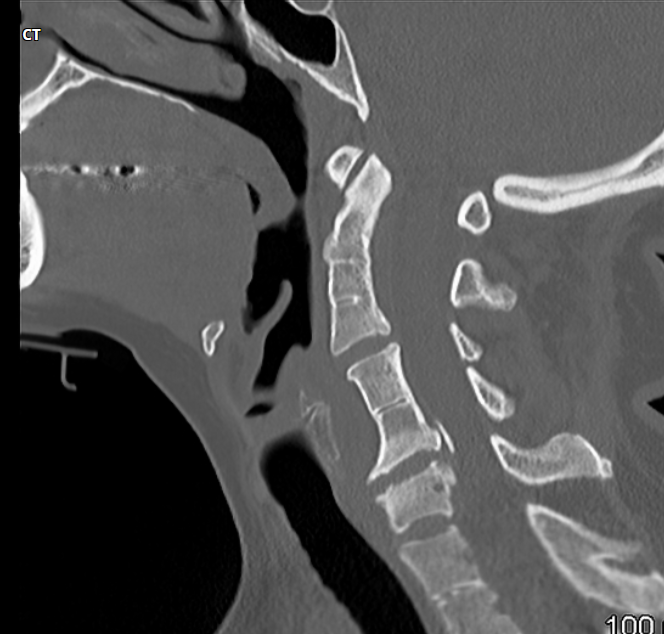

Fratura do processo odontoide

Tipo III de Anderson e D’alonzo.

Envolve o corpo de C2.

Estável, melhor prognóstico;